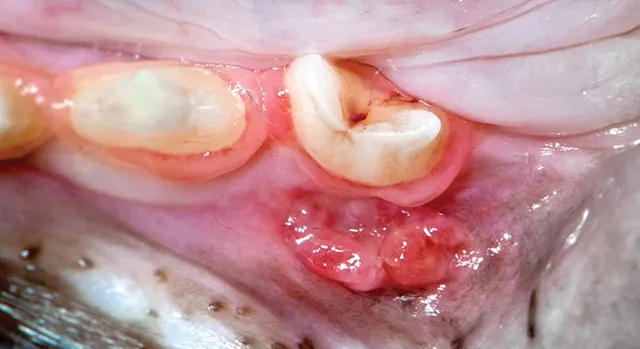

Round area of buccal mucosa ulceration adjacent to tooth.

The following images of erosions and ulcerations illustrate various diseases and conditions.